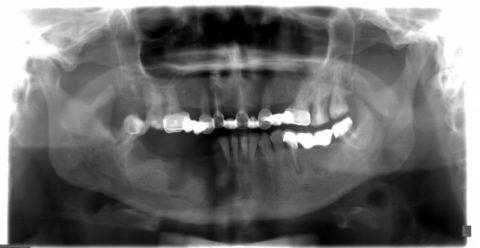

- Рентгенография челюсти. Рентгенологическое исследование - базовый метод диагностики пациентов с подозрением на остеонекроз челюсти. Визуальные изменения костной ткани включают реактивный периостальный остеогенез, уплотнение твердой пластинки альвеолы, утолщение дна верхнечелюстного синуса. С помощью рентгенографии также определяются очаги костной деструкции.

- МСКТ челюсти. На начальных стадиях процесса выявляются «пустые» костные лунки, очаги деструкции челюсти, уменьшение размера периодонтальной щели. Для поздней стадии остеонекроза характерен масштабный очаг деструкции, который выходит за границы альвеолярного отдела челюстной кости. Изредка определяются патологические переломы челюсти.

Проявления острого остеомиелита зависят от пути проникновения инфекции, общего состояния организма, обширности травматического поражения кости и окружающих мягких тканей. На рентгенограммах изменения видны спустя 2-3 недели с начала заболевания.

Компьютерная томография (КТ) — самый информативный метод диагностики остеомиелита челюсти. Это 3D-исследование, которое позволяет определить очаг инфекции и степень выраженности воспаления, его длительность и характер. С помощью КТ можно выявить не только крупные, но и мелкие образования, единичные и групповые, а также проанализировать, насколько далеко распространилась инфекция.

Рентгенография в первую неделю, как правило, не выявляет изменения в кости — в этот период воспалена только верхушка корня зуба. К концу второй недели кость разрушается и становится прозрачнее.

- рентгенограмма в прямой и боковой проекции;

- ортопатомограмма и прицельная рентгенография причинного зуба;

- компьютерная и магнитно-резонансная томография.

Диагностика заболевания начинается со сбора анамнеза и тщательного изучения клинической картины. Для получения более подробных данных назначается рентгенологическое и лабораторное исследование.

При помощи снимка и результатов анализов специалист сможет определить степень запущенности патологии, а это в свою очередь даст необходимые данные для осуществления дальнейшей врачебной тактики.